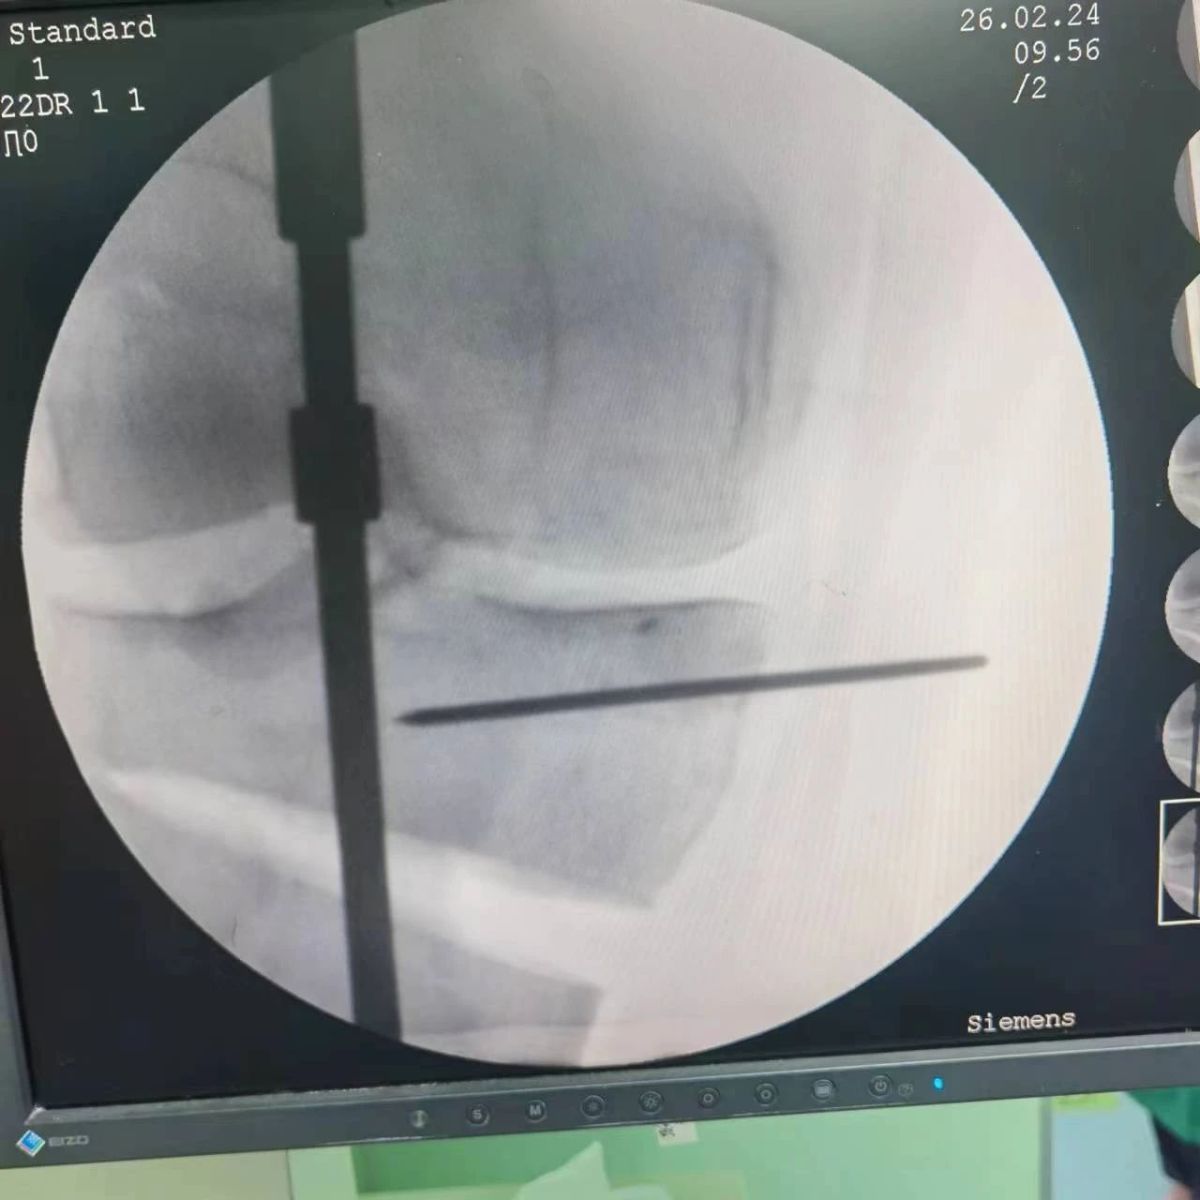

2月26日,漯河市骨科醫(yī)院(漯河醫(yī)專二附院、漯河市立醫(yī)院)膝關節(jié)外科、運動損傷科(骨六科)在保膝治療方面取得了新的突破,李付彬主任帶領岳龍等團隊醫(yī)師,順利完成“計算機精準術前規(guī)劃聯(lián)合3D打印截骨導板輔助脛骨高位截骨治療膝關節(jié)骨性關節(jié)炎”的手術,這在漯河市尚屬首例!

患者為一名45歲男性,查體及X片可見明顯的膝內翻,內翻畸形主要來源于脛骨近端,關節(jié)鏡下可見內側間室軟骨全層磨損,疼痛較重,年紀輕輕幾乎喪失工作能力。對于這種日?;顒有枨蟊容^大的患者朋友,我們盡最大可能給予保膝治療,李付彬主任給患者詳細講解了保膝治療的方案(脛骨近端高位截骨)及預期效果,給患者帶來了極大希望。為了更精確、更微創(chuàng)的治療,李付彬主任團隊緊跟國內外科技前沿,采用計算機精準術前規(guī)劃,并設計3D打印截骨導板,力求給患者帶來更精準、更安全的手術效果。

李付彬主任團隊通過精準術前規(guī)劃,設計目標力線及調整撐開角度,轉化成需要撐開的高度,最終設計出同等高度的填充塊,術中驗證力線調整與術前規(guī)劃完全一致!

鋼板位置、螺釘位置及長度均可通過術前規(guī)劃計算,術中通過定位操作,基本與術前規(guī)劃一致,手術快速高效完成,外側合頁保留完整。無任何并發(fā)癥出現(xiàn)。術后見鋼板位置及力線糾正近乎完美!

OWHTO手術效果依賴于多個數(shù)據(jù)參數(shù),比如:截骨的入點、合頁位置的選擇、截骨線的深度、截骨線的方向、撐開的距離等,依托計算機術前精準規(guī)劃和3D打印導板可輔助醫(yī)生精準控制上述參數(shù),使截骨更準確,真正達到精確的力線調整,減少術中透視次數(shù),縮短手術時間并降低手術風險,從而使得OWHTO得到更好的應用,造?;颊?。